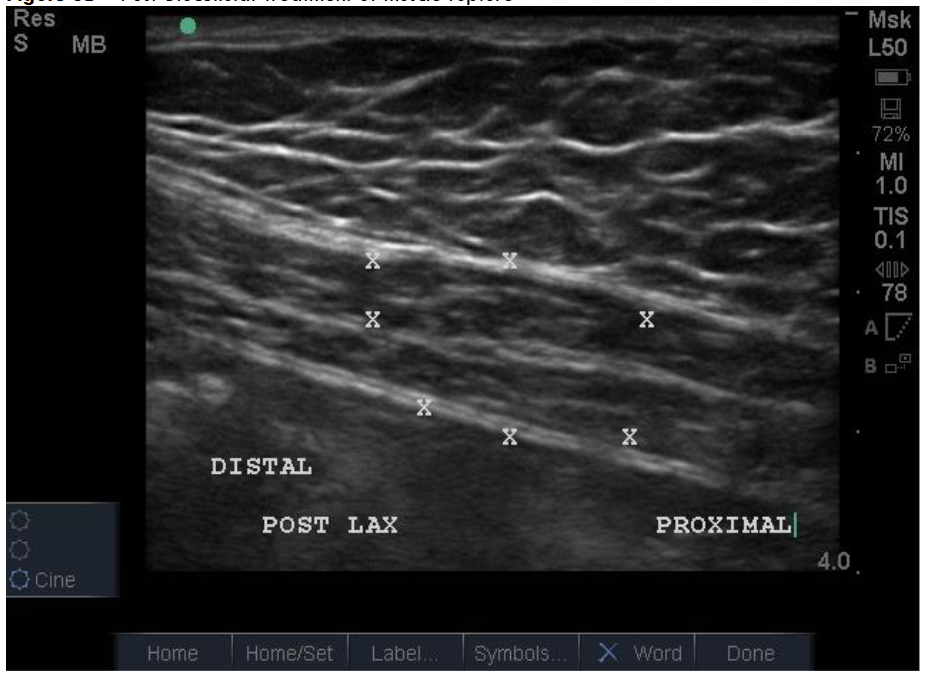

Muscular/Scar Repair: The ability of the biocellular mixture in the repair of torn, damaged or failed muscular structures is quite remarkable. This is accentuated in light of the difficulties relative to internal muscle repair of damage as seen in trauma or invasive surgery. Often rapid responses are realized, with both avoidance of scarring OR the reduction of scarring present has been well shown in many clinical cases. With enhanced vascularity and perfusion within the damaged muscular tissues, limited or less scar formations are important advantages. Some Providers define a ”toxic” inflammatory reactions as those that lead to tissue scarring. This is seen in unstable or excessive inflammatory scar reactions which are not desirable. Avoidance of excesses or hypertrophic scarring is a clear advantage to wound healing and long-term outcomes for patients. Nanofat stem/stromal elements are capable of forming smooth, skeletal and cardiac muscle. Biocellular therapy helps a more stable and less inflammatory environment. This coupled with the existing damaged muscle can lead to excellent reformation and return to function. This modality is becoming very common to include direct intramuscular guided placements to improve the internal architecture (sonographic echotexture restoration), and confirmed with dynamic testing of the musculature during the ultrasound from diagnostic and treatment when tracked in follow up examinations.

Figure 8A: Traumatic Rupture Right Rectus Abdominus (American Football Helmet) Defect, Pre-Treatment at 48 hours. Figure 8B: Post-Biocellular treatment of muscle rupture, patient returned to full-contact professional football within 2 weeks pain free. Treatment was with use tSVF + HD PRP+ (activated with human recombinant thrombin) at 70% tSVF and 30% HD PRP (by volume). Patient pain free at 1 week, returned to full contact in two weeks without recurrence or pain. Post-treatment exam at approximately 4 months. NOTE: no visible scarring resulting from intramuscular tear.